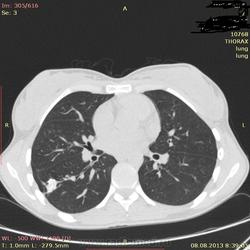

Здраствуйте, коллеги. Нужна ваша помощь молодая девушка 21 г. в течении 2-х лет беспокоит субфибрильная температура, период.гол. боль. В прошлом году сделала ОГК зак: туберкулема. Ей сказали что она перенесла тбс. на ногах, лечение не принимала. Сдавала все анализы без изменении.Родная сестра 3 года назад перенесла тбс.

Туберкулёма в 6-ке.

Распада не вижу, очагов отсева тоже. Контроль и к фтизиатру.

По показанным изображениям данных за активность нет, но без дайкома однозначно не сказать. Посмотрите в MIP при толщине среза 4-6 мм очаги. Если у девушки иммунодефицит любого генеза, то картина даже через несколько дней может кардинально поменяться, так что в любом случае конс.фтизиатра.

Справа в С6 - неправильной округлой формы образование повышенной интенсивности с включениями извести. Данное образование связано с корнем лёгкого бронхо-сосудистой "дорожкой". Рекомендовано анализ мокроты на МБТ!